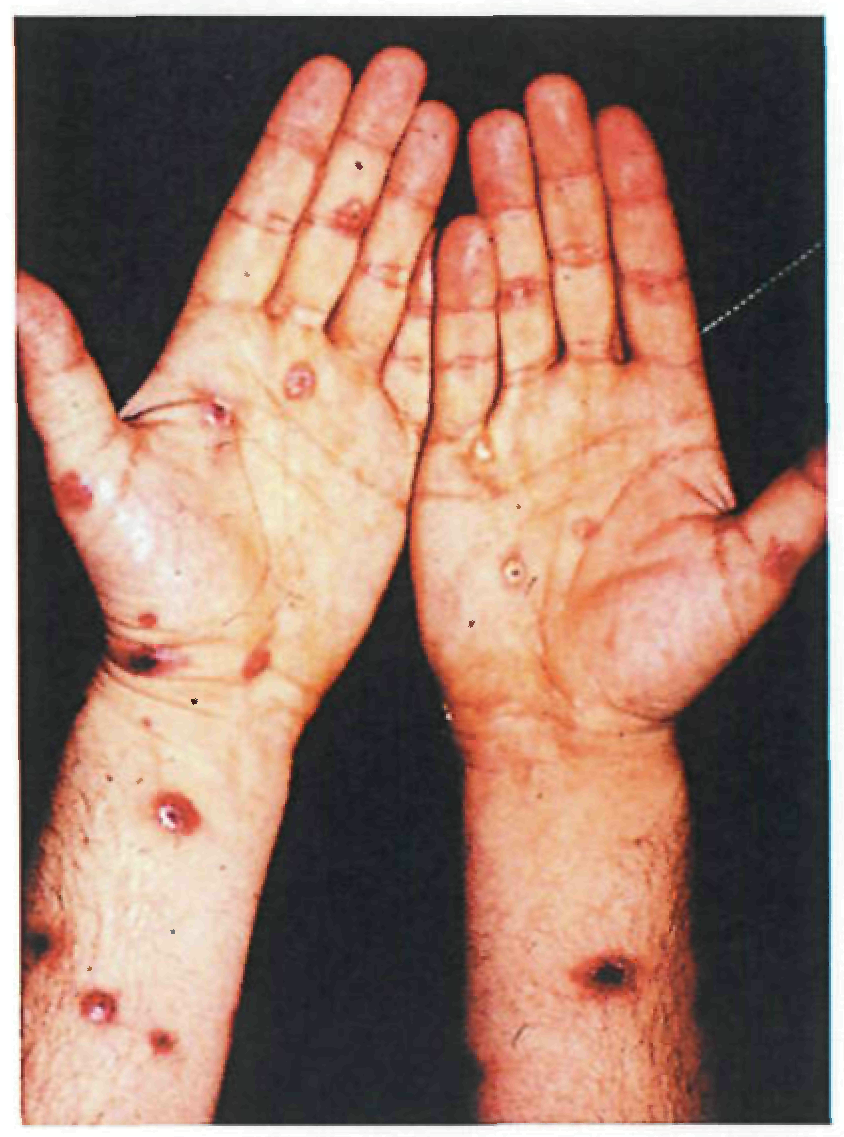

Период высыпаний

На 3-4-й день болезни температура тела снижается до субфебрильной, одновременно на коже головы (прежде всего на лице) и на слизистых оболочках полости рта, гениталий, конъюнктивы, роговицы глаз появляются необильные элементы сыпи. Энантема на слизистых оболочках полости рта обычно предшествует появлению экзантемы. Первые элементы сыпи обычно появляются на лице, быстро распространяясь на верхние конечности, а затем - на туловище и нижние конечности, поражая ладони и подошвы. Распространение экзантемы имеет центробежный характер - на туловище элементов меньше, чем на лице и конечностях.

В 95% случаев сыпь поражает лицо, в 75% - ладони и подошвы, что является отличительным признаком заболевания. Также поражаются слизистые оболочки полости рта (в 70% случаев), половые органы (30%), конъюнктива и/или роговица (20%). У части пациентов имеет место проктит с поражениями перианальной области изолированно или в сочетании с высыпаниями в области гениталий [39]. Количество элементов сыпи варьирует от единичных до нескольких тысяч [13].

| Сифилис вторичный | Может присутствовать в части случаев | Через 2-10 недель после появления твердого шанкра | Пятна, папулы круглой или овальной формы, с четкими границами. Папулы нередко шелушатся. У ослабленных пациентов, страдающих алкоголизмом, наркоманией, туберкулезом, ВИЧ-инфекцией может наблюдаться пустулезный (оспенновидный) сифилид: шарообразные пустулы величиной с горошину, центр которых быстро засыхает в корку, расположены на плотном основании синюшно-розового цвета. | Пятна и папулы диаметром 0,5-1,0 см | Этапность распространения не характерна | Поражение шейных, затылочных, паховых, локтевых, подмышечных лимфоузлов. | На коже туловища, границы роста волос, шея, ладони и подошвы, носогубный треугольник, вокруг заднего прохода, половые органы. Локализация пустулезного (оспенновидного) сифилида: лицо, особенно лоб, туловище, конечности. |